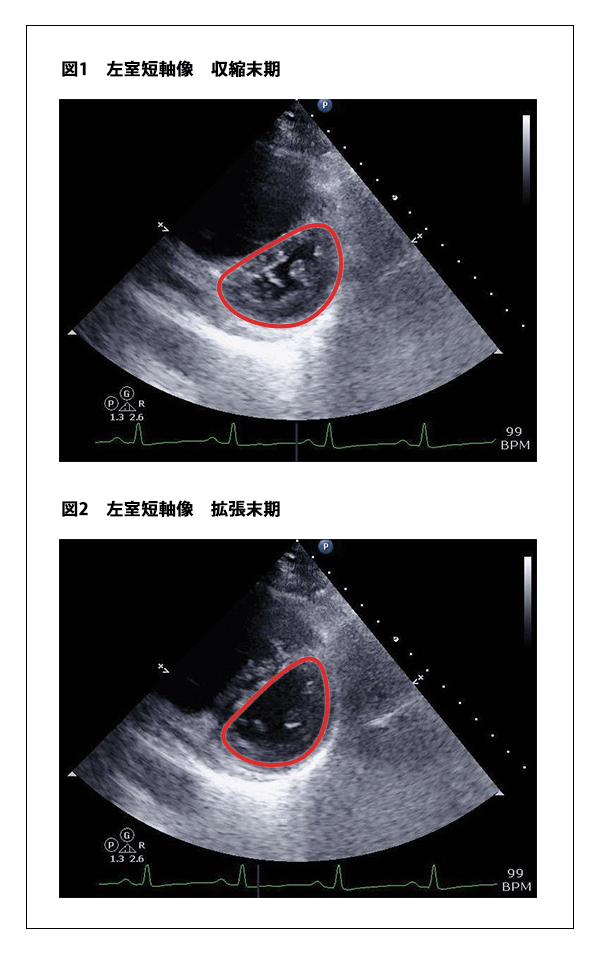

さらに、PEの心エコー所見では、Bさんのような一部の肺動脈に急性の塞栓が生じたことで室圧負荷を反映した右室による左室の圧排所見(D-shapeと呼ばれることが多い)を認めます(図1、2の赤丸部分参照)。